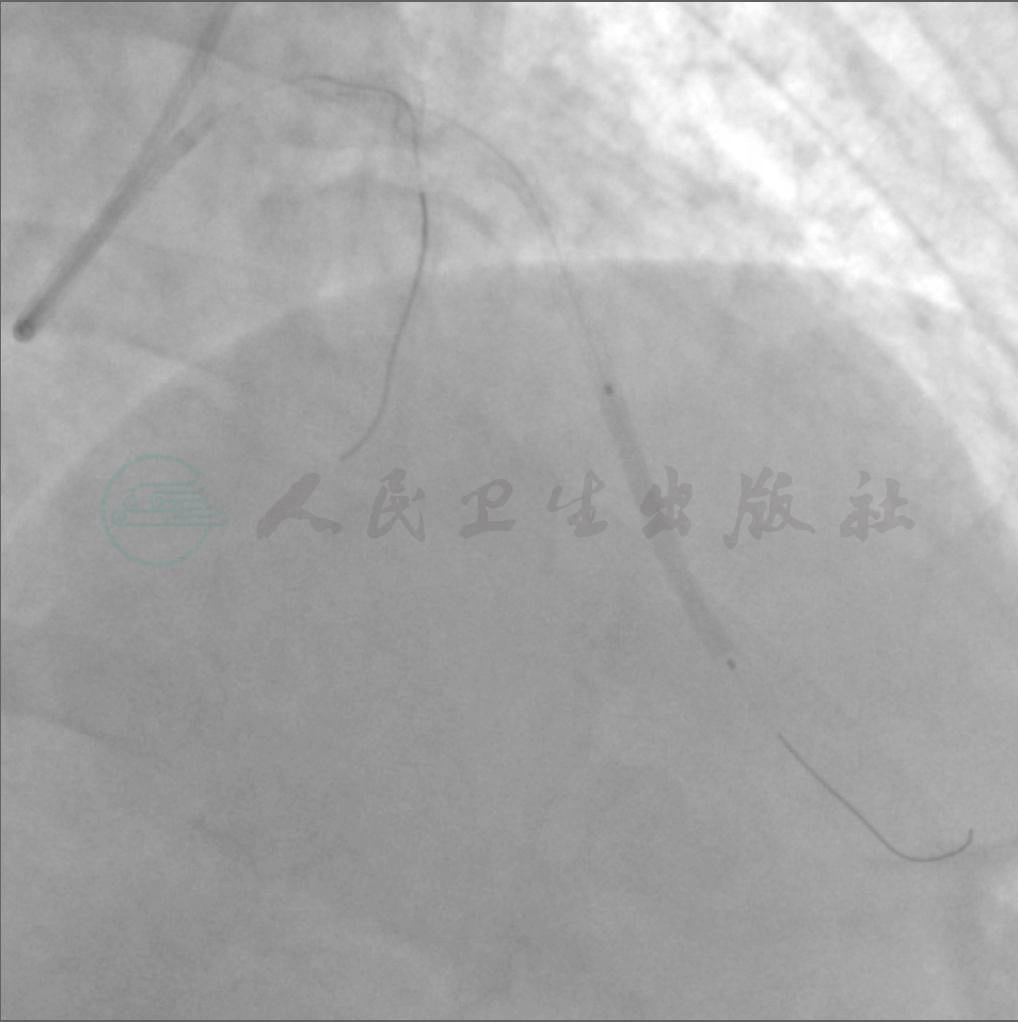

图2 2011年10月,LAD开口闭塞,无残端

图3 2011年10月,LAD开口闭塞,无残端。 LCX远端90%狭窄至95%狭窄